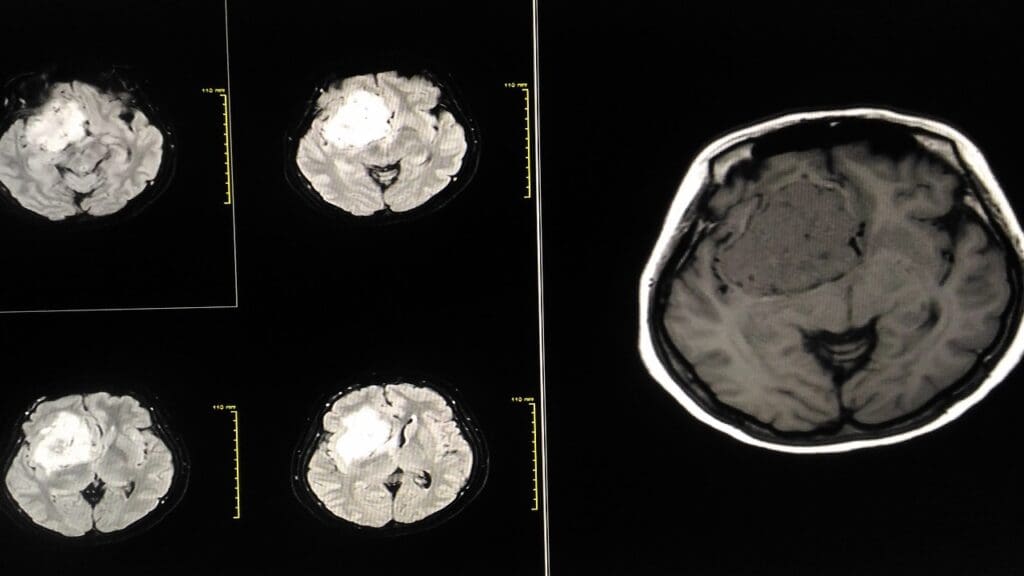

Doctors use MRI to measure brain tumors. They record these measurements in millimeters or centimeters. For tiny tumors, millimeters are better. Bigger ones are measured in centimeters.

Diagnostic Challenges: Interpreting Brain Scans

Reading brain scans is a tough job. We use MRI to find brain tumors, but the results can be tricky.

Understanding “Shadows” on Brain Scans

A “shadow” on a brain scan might worry you, but it doesn’t always mean cancer. We must look closely at these signs. Sometimes, a shadow could mean a tumor, but other times it might be something harmless or an imaging glitch.

Differentiating Between Tumors and Other Brain Abnormalities

Telling tumors apart from other brain issues is key to getting a correct diagnosis. We use advanced MRI sequences to learn more about the tumor.

Advanced Imaging Techniques for Accurate Diagnosis

Tools like functional MRI and diffusion tensor imaging give us important details. They help us make better diagnoses and plan treatments.